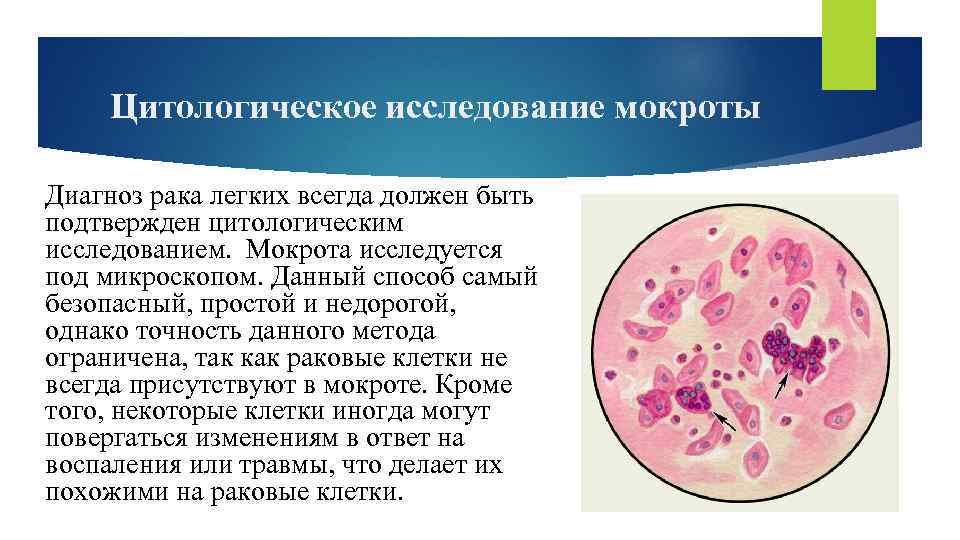

Цитологическое исследование мокроты Диагноз рака легких всегда должен быть подтвержден цитологическим исследованием. Мокрота исследуется под микроскопом. Данный способ самый безопасный, простой и недорогой, однако точность данного метода ограничена, так как раковые клетки не всегда присутствуют в мокроте. Кроме того, некоторые клетки иногда могут повергаться изменениям в ответ на воспаления или травмы, что делает их похожими на раковые клетки.

Цитологическое исследование мокроты Диагноз рака легких всегда должен быть подтвержден цитологическим исследованием. Мокрота исследуется под микроскопом. Данный способ самый безопасный, простой и недорогой, однако точность данного метода ограничена, так как раковые клетки не всегда присутствуют в мокроте. Кроме того, некоторые клетки иногда могут повергаться изменениям в ответ на воспаления или травмы, что делает их похожими на раковые клетки.